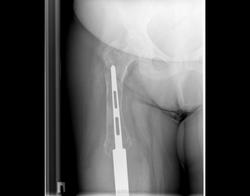

Снимки 4,5,6 пациентки, которой была сделана резекция бедренной кости с эндопротезированием коленного сустава 30 лет назад по поводу остеосаркомы. Расшатывание эндопротеза клинически стало себя проявлять 5 лет назад (снимок 4), далее довольно быстро прогрессировало, что по-видимому усугубилось присоединившимся остеомиелитом (снимки 5, 6 - теперешние). Пришлось выполнить ампутацию, тем не менее, человеку дали 25 лет нормальной, полноценной жизни.